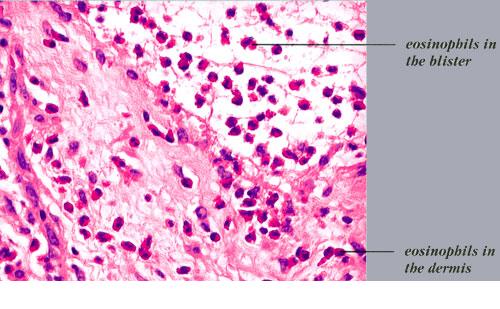

Histopathology.

In early lesions, papillary dermal edema in combination with a cell-poor or cell-rich perivascular lymphocytic and eosinophilic infiltrate is present. The blister arises at the dermal-epidermal junction . In the cell-rich pattern, which correlates clinically with blisters arising on erythematous skin , eosinophilic papillary abscesses may develop with numerous perivascular and interstitial eosinophils intermingled with lymphocytes and neutrophils in the superficial and deep dermis. Early lesions may have the histologic features of eosinophilic cellulitis (Well’s syndrome). Eosinophilic spongiosis may occur. The cell-poor pattem is observed

when blisters develop on relatively normal skin , in which there is usually a scant perivascular lymphocytic infiltrate with few eosinophils, some scattered throughout the dermis and others near the epidermis. The blister contains few inflammatory cells. Epithelial migration and regeneration may result in an intraepidermal split in older blisters. Similar to pemphigus vegetans, a hyperplasia of the epidermis, subepidermal bullae, and accumulations of eosinophils and lymphocytes may be seen.